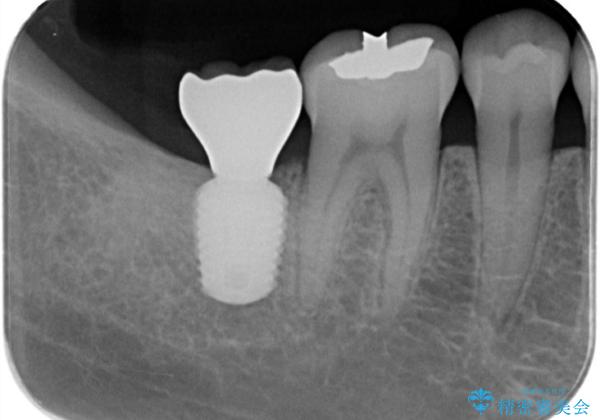

【インプラント】虫歯が大きくて歯を抜いた。

- 奥歯の虫歯が大きいため保存不可となった患者様です。

矯正の治療も進めながら、インプラントを埋入して補綴をおこなっています。

骨幅があったため、太いインプラント体を使用しています。

今回はスクリューリテインにて修復を行なっています。